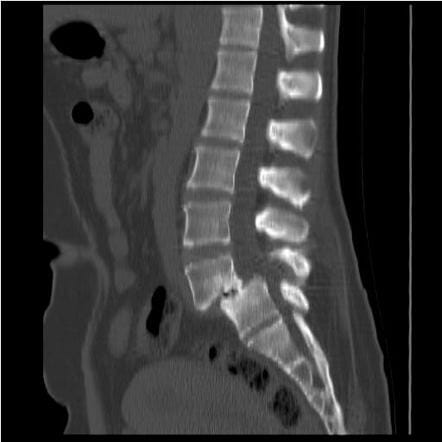

CT scan ในผู้ป่วยหมอนรองกระดูกสันหลังเคลื่อน

- สามารถตรวจพบความผิดปกติของชิ้นส่วนกระดูกสันหลังได้ละเอียดกว่าการถ่ายภาพรังสีเอกซเรย์ทั่วไป

- ช่วยในการวางแผนการผ่าตัดโดยละเอียด